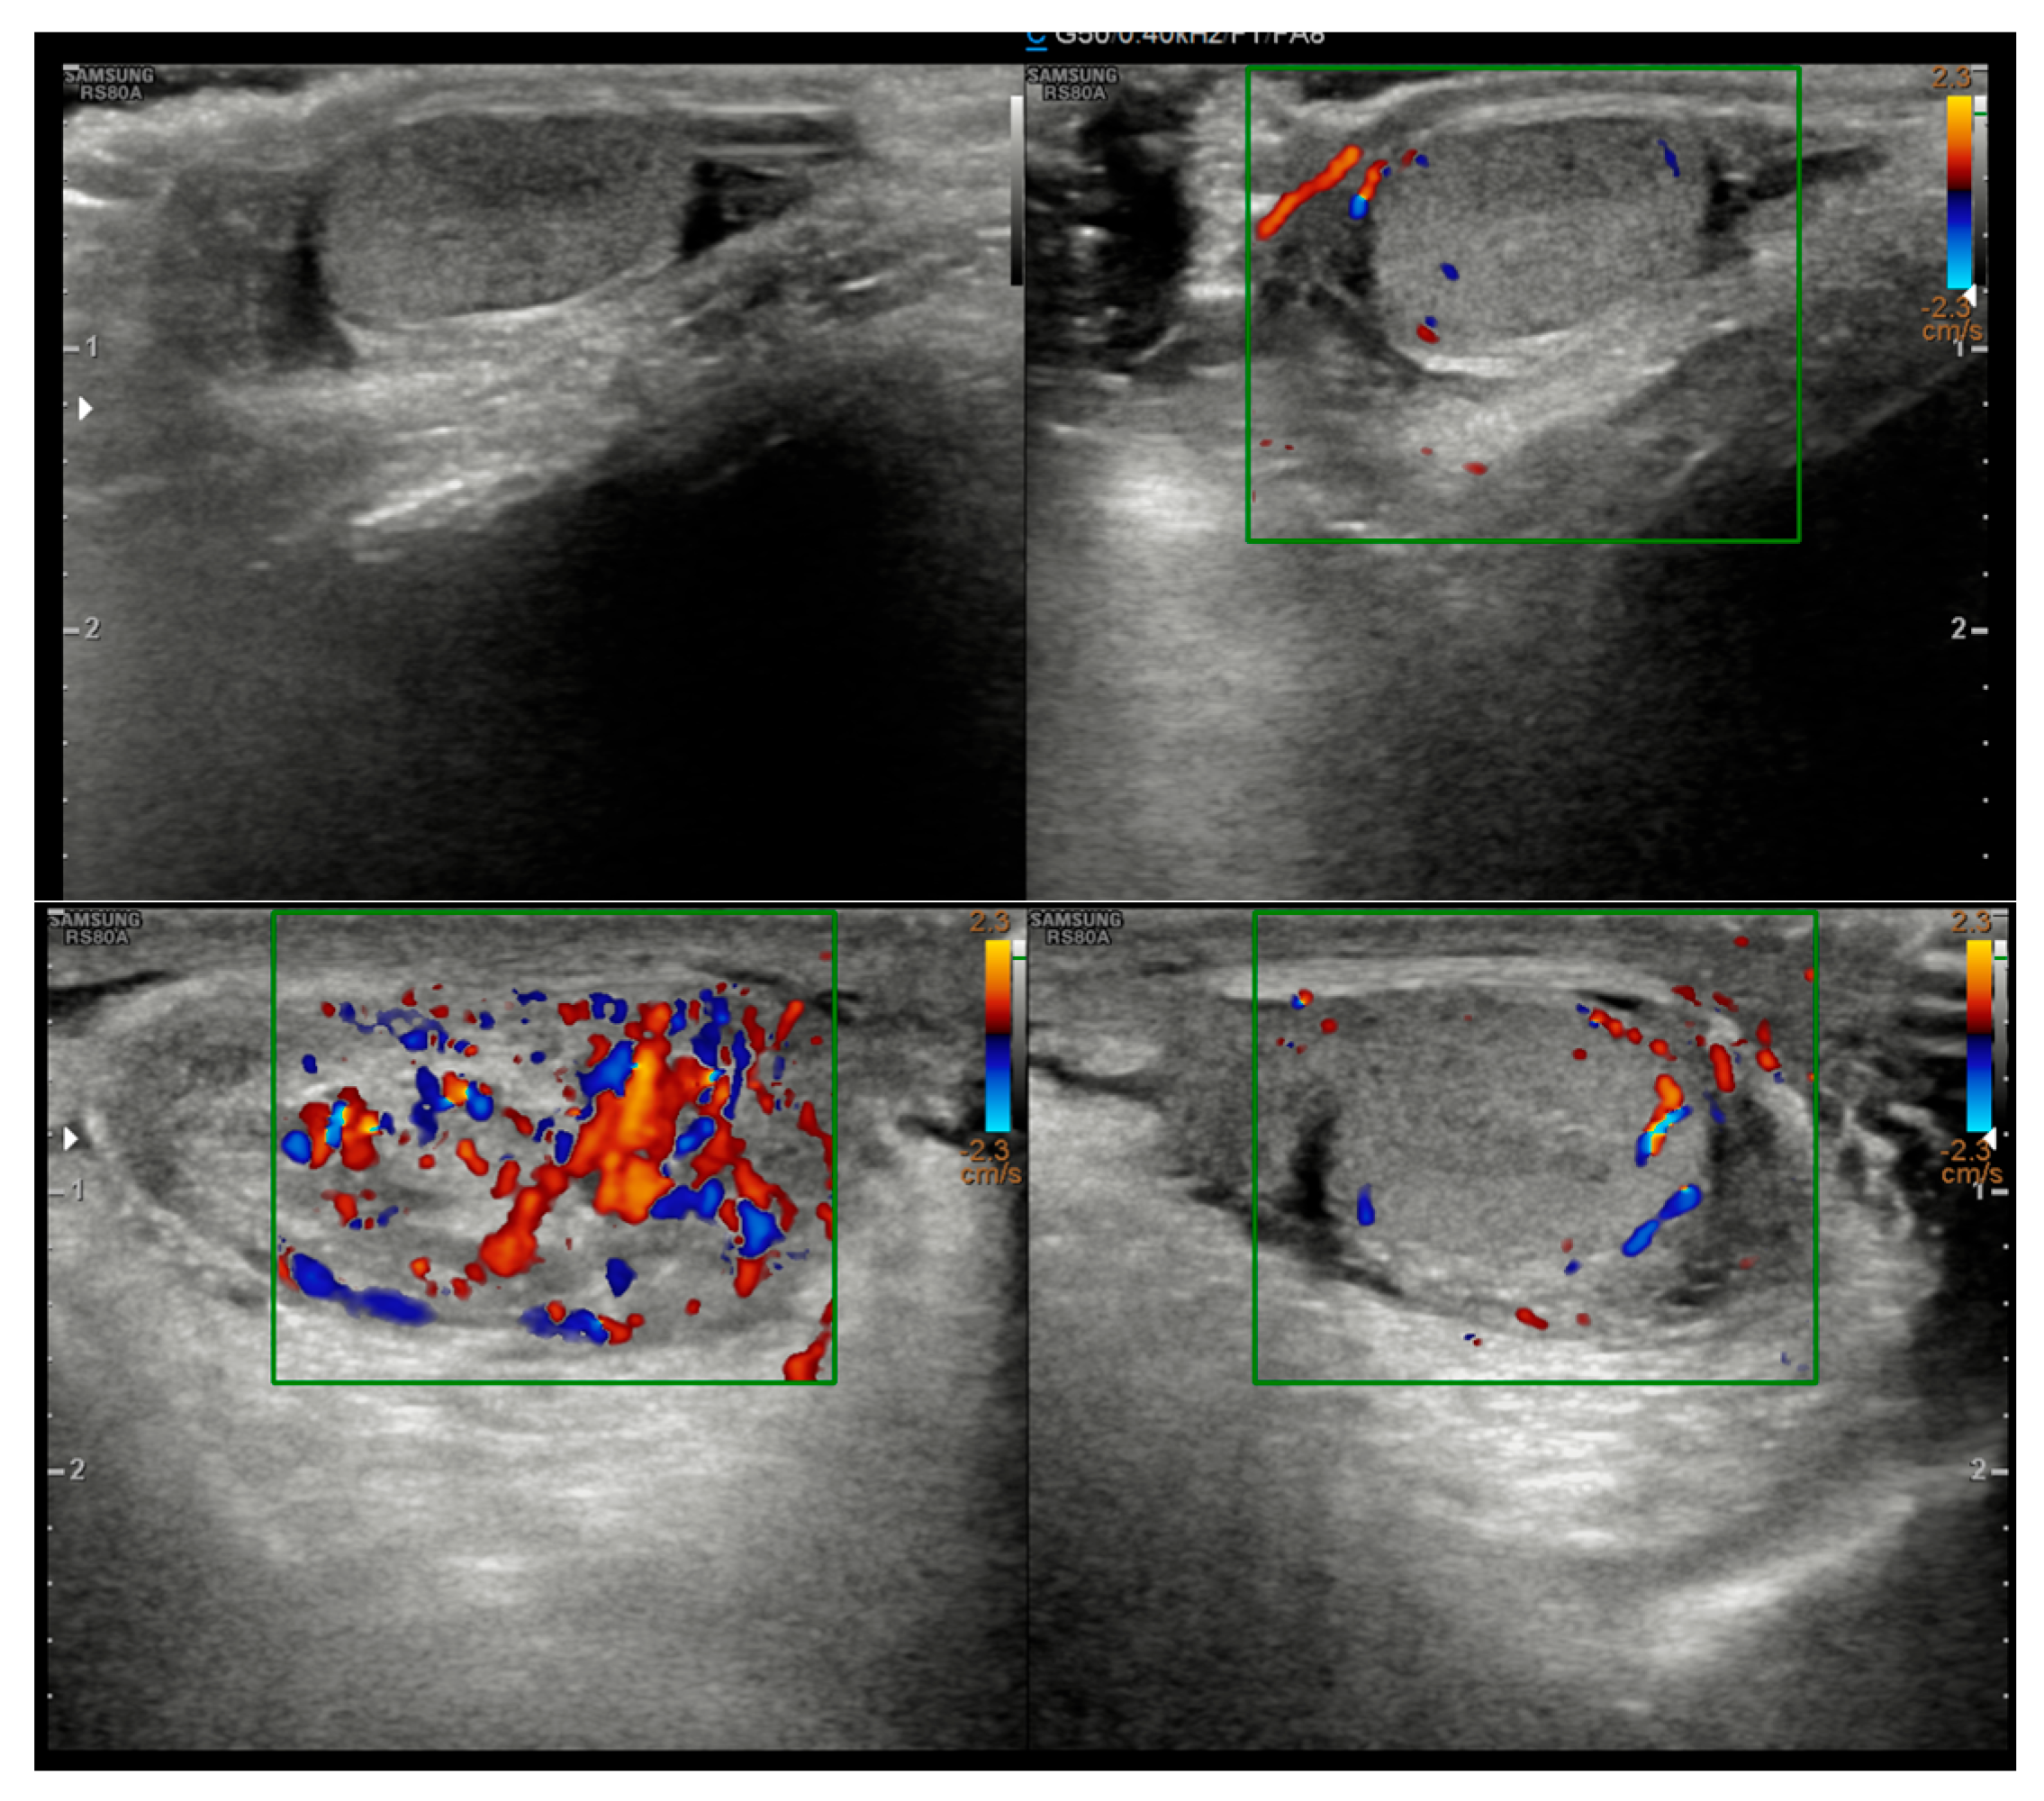

2. Case Presentation